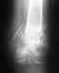

Норильск. Диагноз от 02.11.2008 г.: множественная травма. Открытый внутрисуставной оскольчатый перелом дистального методиафиза левой бедреной кости со смещением отломков. Осложненные развития массивного посттравматического раневого дефекта мягких тканей нижней трети левого бедра левой подколенной области с переходом на верхнюю треть голени.Закрытый перелом диафиза правой бедренной кости со смещением отломков. Открытый оскольчатый перелом костей левой голени со смещением отломков.Рваные раны левого бедра и левой голени.

Операции: Открытая репозиция, мос костей левой голени; открытая репозиция, мос правой бедренной кости; открытая репозиция, мос левой бедренной кости. Катетеризация справа подключичной вены. Некрэктомия левого бедра, левой подколенной области, задней поверхности левой голени. Свободная кожная пластика расщепленным кожным лоскутом.

Последняя операция была 09.10.2009 г. Редрессация правого коленного сустава, этапное удаление мк, проволочного серкляжа из нижней трети правой бедренной кости.

• Кликните для загрузки файла 5.jpg